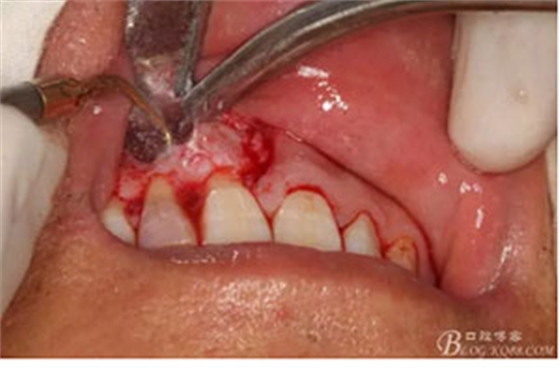

圖6.行唇側(cè)角形切口(11近中垂直切口+齦溝內(nèi)水平切口)垂直切口距離前庭溝約1~2mm。這樣可以減輕術(shù)后腫脹。

圖7. 角形切口中的齦溝內(nèi)切口情況:11號刀片伸進(jìn)齦溝內(nèi)斜切。